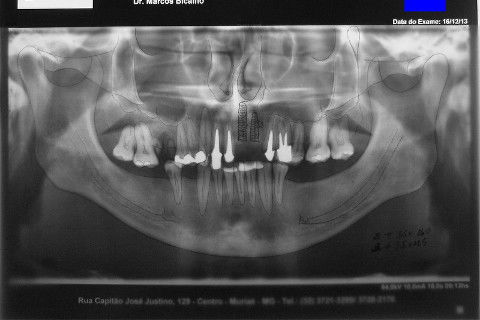

Paciente apareceu em meu consultório em dezembro/2013 para resolver problema de insatisfação com ponte fixa provisória anterior, realizada há 9 anos atrás (2004)...pretendia realizar somente a reabilitação em maxila/anterior, não contava com outros problemas com maior gravidade na sua boca, o máximo que citou foi a indicação para a exodontia do 16...

Cirurgia realizada hoje de manhã...No planejamento percebi medindo espessura do rebordo com especímetro que as medidas não estavam muito boas, ou o ideal, em torno de 4,5 a 5 mm ate´o terço médio do rebordo e melhorava no final, com 6 a 7 mm. Optei então por uma pequena expansão usando os expansores rosqueáveis. Aconteceu uma pequena fenestração na hora da fixação dos implantes, especialmente na região do 22 que fraturou o início da tábua óssea, mas não me preocupei porque não foi mais do que 2 mm de fratura em direção apical, o implante ficou infraósseo e com boa estabilidade (60 N no 21 e 40 N no 22). Esta fratura tb não deixou osso completamente solto, foi do tipo galho verde, deixei em posição e suturei normalmente. Só não fiz e nem estava planejado carga imediata mesmo, mais pelo motivo da oclusão inadequada do caso.